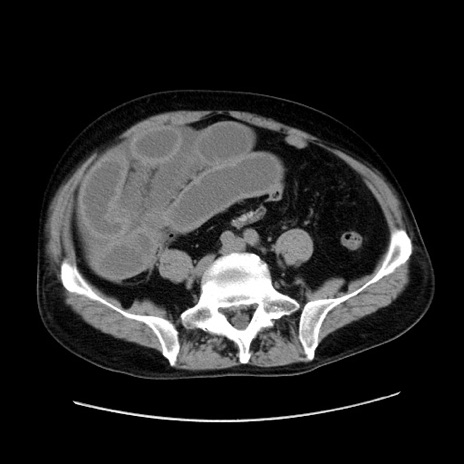

症例30(横断像)

【症例】80歳代男性

【主訴】臍周囲痛

【現病歴】約6時間前から臍下部痛が出現。次第に腹部膨隆・背部痛も生じてきたため来院。背部痛の場所は変化しない。

【身体所見】意識清明、BT 36.3℃、BP  131/87mmHg、P 87bpm、SpO2 100%(RA)、臍周囲自発痛・圧痛あり、反跳痛なし、自発痛部位に一致して板状硬あり、腹部膨隆、腸雑音減弱、CVA tenderness両側陰性。

【データ】WBC 19600、CRP 0.33